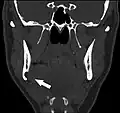

-

Stafne bone cavity seen on coronal CT -